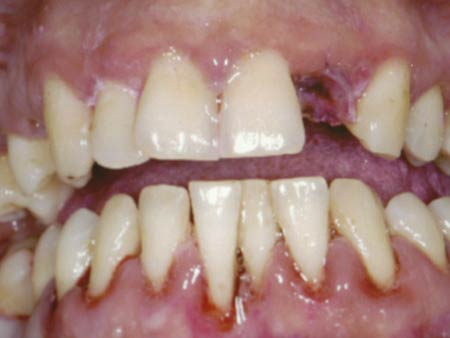

Periodoncia

El mas frecuente problema de las encías es la piorrea o periodontítis: esuna enfermedad muy común que, si no se trata adecuadamente, provoca que los dientes sangren, comiencen a moverse y acaben por perderse.

Al no provocar dolor, se trata de una afección que suele pasar desapercibida y el paciente no le da importancia con lo que, la enfermedad avanza, y tiene como consecuencia la pérdida de las piezas. Sin embargo, con un tratamiento adecuado y las consiguientes revisiones periódicas conseguimos que la piorrea se detenga y conservar los dientes.